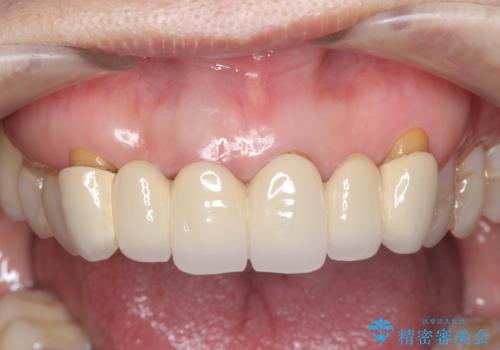

不自然な前歯ブリッジ ジルコニアブリッジによるやり替え

丁寧に現在装着されているブリッジを除去後、精度の高いジルコニアブリッジで審美性の改善を計画します。

前歯に限らず拡大鏡を用いた精密な形成・シリコンを用いた精度の高い印象を徹底することで治療全体の質を高め、審美性だけでなく長期的な予後を期待することができます。